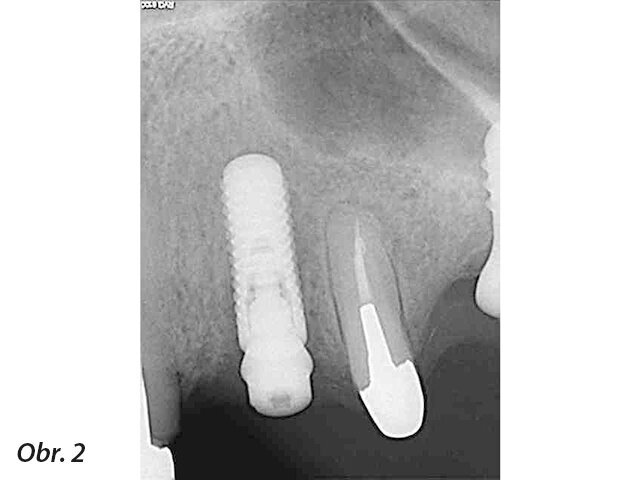

Obecně termín „periapikální léze u implantátu“ (PIL – periapical implant lesion) popisuje radiografický nález kolem apexu implantátu, bez vztahu k dalším periimplantátovým tkáním nebo sousedním zubům. Klinické vyšetření potíží pacienta nemusí vždy indikovat patologický nález, a pokud ano, tak se definice tohoto pojmu překrývá s „retrográdní periimplantitis“ (RPI – retrograde peri-implantitis). RPI má podobnou definici, ale je doprovázeno stížnostmi pacienta a často i klinickými nálezy (obr. 1–3).

RPI manifestuje skrze radiografické a také rozmanité klinické nálezy. V případě RPI je zde přítomna retrográdní infiltrace patologických mikroorganismů, které osídlí apex implantátu. Tato infiltrace často pochází od sousedního zubu, není to ovšem jediná příčina RPI. Další příčiny mají vztah k operačnímu protokolu, protetice a plánování implantace. Ve většině případů vede k diagnóze kombinace více než jednoho faktoru. Laterální defekty, mobilita implantátu a pooperační zánět vztahující se ke zbytku fixtury implantátu nebo zánět periimplantátových tkání jsou z této definice vyloučeny.

Jak PIL, tak RPI se často objeví jako náhodný radiografický nález až léta po zavedení implantátu a protetické rehabilitaci. Pokud jsou doprovázeny klinickými nálezy jako je pozitivní poklep, stížnosti na skus nebo syndrom bolesti, rozlišujeme dvě doby: a) po šesti týdnech od zavedení a b) čtyři až osm týdnů po zatížení. Stížnosti na bolest za delší dobu od zatížení jsou ve většině případů indikací křížové kontaminace od sousedních zubů.